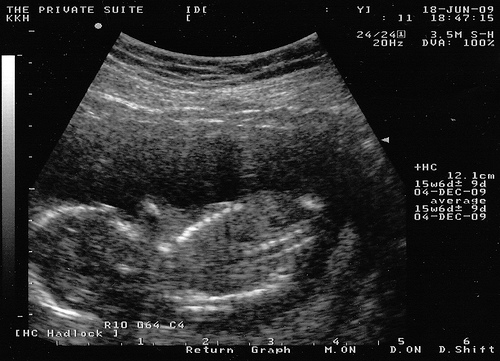

УЗИ: 15-ая неделя беременности

На этой неделе происходит оценка мышечного слоя матки. В норме он должен быть тонким и равномерным.

Плод начинает все больше напоминать человека: ушные раковины и глаза перемещаются на свои привычные места. Волосы плода начинают получать пигмент, и вскоре станет очевидно, какого они будут цвета после рождения. Ребенок начинает глотать околоплодные воды, что является нормальным процессом. Таким образом, малыш готовится к жизни вне материнского организма.